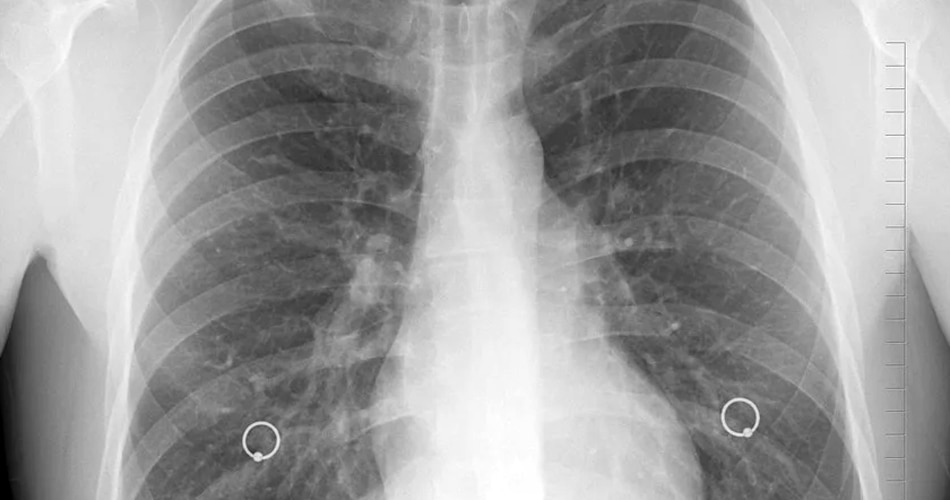

फेफड़े खराब होते हैं

• 3/8

डॉक्टर्स का कहना है कि Candidiasis का इलाज काफी आसानी से किया जा सकता है. वहीं ज्यादातर मामलों में ये इंफेक्शन जानलेवा भी नहीं होता है. इस बारे में डॉक्टर कपिल बताते हैं कि Candidiasis को आसानी से पहचाना जा सकता है. ये बस तभी खतरनाक साबित हो सकता है जब मरीज अपने अंदर दिख रहे तमाम लक्षणों को पूरी तरह से नजरअंदाज कर दें.